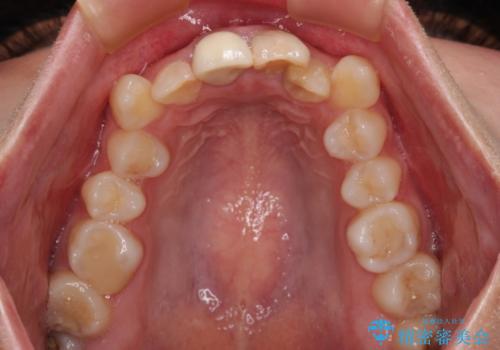

- 学生の頃に神経を取り除いた前歯の変色と、色合いの悪いかぶせ物が気になるとのことで来院された患者様です。

レントゲン写真より、歯根の炎症が認められず、土台もしっかりと植立されていたため、仮歯に置き換えた後にオールセラミッククラウンにて補綴することとしました。

当初は矯正治療を希望されていましたが、関西圏への転居と結婚式が間近であるということから、前歯の補綴治療のみを行うこととしました。